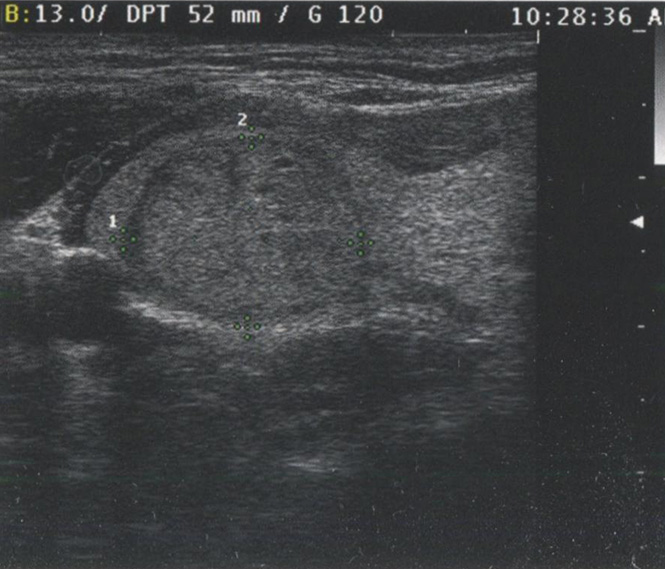

И хотя более высокие частоты дают лучшее разрешение, глубина визуализации с увеличением частоты снижается. В современных УЗ-аппаратах для исследования ЩЖ используется достаточно высокая частота — 16 МГц. Однако при этой частоте исследование можно провести лишь на глубину до 5 см. Визуализация более глубоких структур, как и при УЗИ органов брюшной полости или малого таза, требует более низкой частоты. У тучных пациентов или при исследовании очень глубоких структур для адекватного проникновения луча и визуализации глубоких структур шеи может потребоваться частота 5-7,5 МГц. На рис. 2.22 и рис. 2.23 сравниваются изображения при частоте 7,5 и 13 МГц. Видно, что детализация проксимальных структур при более низкой частоте снижается.

Рис. 2.23. Сравнение изображений при частоте 7,5 и 13 МГц. На этом изображении при частоте 13 МГц узел визуализируется намного четче. Сравните с рисунком 2.22